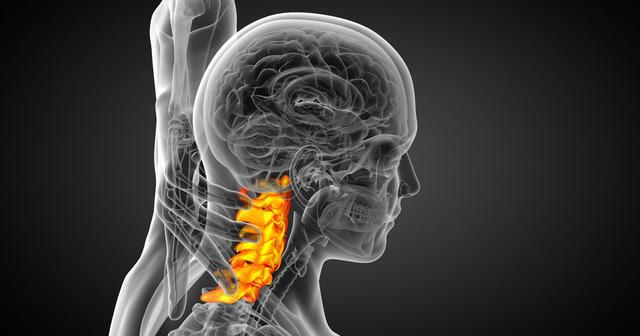

人類進化從爬行到直立行走解放了雙手,卻帶來了很多各種類型的脊柱疾病。頸椎病是其中非常常見的一種脊柱關節疾病。隨著人類生活方式的改變,頸椎病發病現在也逐漸低齡化。很多年輕上班族、學生都開始經常感覺頸項疼痛,還有伴有手指手臂麻痺等頸椎病症狀的出現。

那我們今天就來簡單了解一下頸椎病,希望能對頸椎病初期患者起到部分指導作用。首先,頸椎病在臨床是分好幾型的,看看你是屬於哪一種。

1. 頸型:很多青年人頸椎病最開始都是以頸型發作的。就是出現反復發作的落枕,或經常頸部酸脹疼痛不適感,伴稍有頸部轉動不靈活和頸項部局部壓痛點。

2. 神經根型:是指椎間盤突出或者骨贅壓到了神經根,症狀一般為頸部疼痛,手指麻木、皮膚感覺能力減退,嚴重者還可出現手的大小魚際和骨間肌萎縮。

3. 椎動脈型:是指椎間盤突出或者骨贅壓到了椎動脈,椎動脈受壓會影響到大腦供血,所以症狀一般是頭顱旋轉引發的眩暈,偏頭痛,耳鳴耳聾,健忘,眼睛乾澀視物模糊等。若頸部轉動忽然引發一定位置缺血,還可出現猝倒。

4. 交感神經型:由於頸椎盤有較多交感神經節,如果頸椎間盤突出或者骨贅刺激到了交感神經,會出現很多交感神經症狀,這種型比較複雜,可以出現的症狀也很多。可以影響到五官出現視物模糊、流淚等;影響到頭部出現頭痛、頭麻等,還可以影響到心臟,出現心臟不適胸悶、心動過速等,還可影響到血壓,出現高血壓,且對降壓藥無效;還可出現出汗障礙、雷諾綜合徵等。

5. 脊髓型:是頸椎間盤突出或者骨贅壓迫到了脊髓,常見症狀有上下肢無力感,逐漸出現走路踩棉花感,步態拙笨甚至跌倒。後期還可出現排二便障礙。

6. 混合型:是指前面所述五型中有兩種以上合併存在,在臨床上此型最多見。因為以上這些受壓組織在解剖上都是密切相連的,所以很多情況下,上面這些組織都會同時受到椎間盤不同程度的刺激壓迫,出現混合的症狀。

由上可知,頸椎病的表現形式可以多種多樣,小的突出或骨贅可能只壓迫一種組織,臨床出現症狀也少,大的骨贅可以壓迫多個組織,臨床表現也複雜。如初期為頸肩臂疼痛等神經根症狀,數年後出現頭暈、耳鳴等椎動脈或交感神經受累症狀。

很多人覺得頸椎病是小病,但是如果頸椎病嚴重的話,壓迫到交感神經影響到心臟,可以出現頸源性心髒病,出現心絞痛;壓迫到椎動脈,可能會急轉項時,引發忽然暈倒;壓迫到脊髓,猛地跌倒可能會造成脊髓的損傷,出現肢體癱瘓。這些都是可能的潛在危害。

現在越來越多年輕人就患有頸椎病了,頸椎病又具有較強的隱匿性,各種發病表現也不一樣不易被察覺,加上很多人對頸椎病認識不足,這些都會導致嚴重的後果,所以還是得引起重視。

如果還是頸型頸椎病,一定要生活各方面多注意,以防後期形成更嚴重的壓迫性頸椎病。只要出現頸椎病的典型症狀,就要馬上開始診斷,正規治療,傳統治療非手術治療為優先。